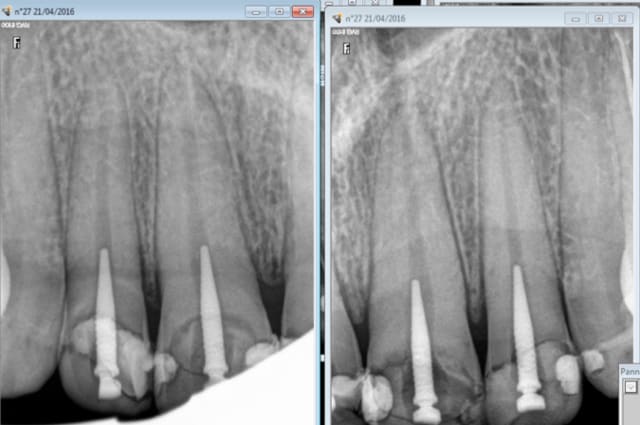

chicot29

21/04/2016 à 18h58

Ben tiens, de mieux en mieux On ne change pas une équipe qui gagne. Enfin bon ca a ses limites motif de la consult à votre avis ? -)

Capture d e cran 2016 04 21 16.54 - Eugenol